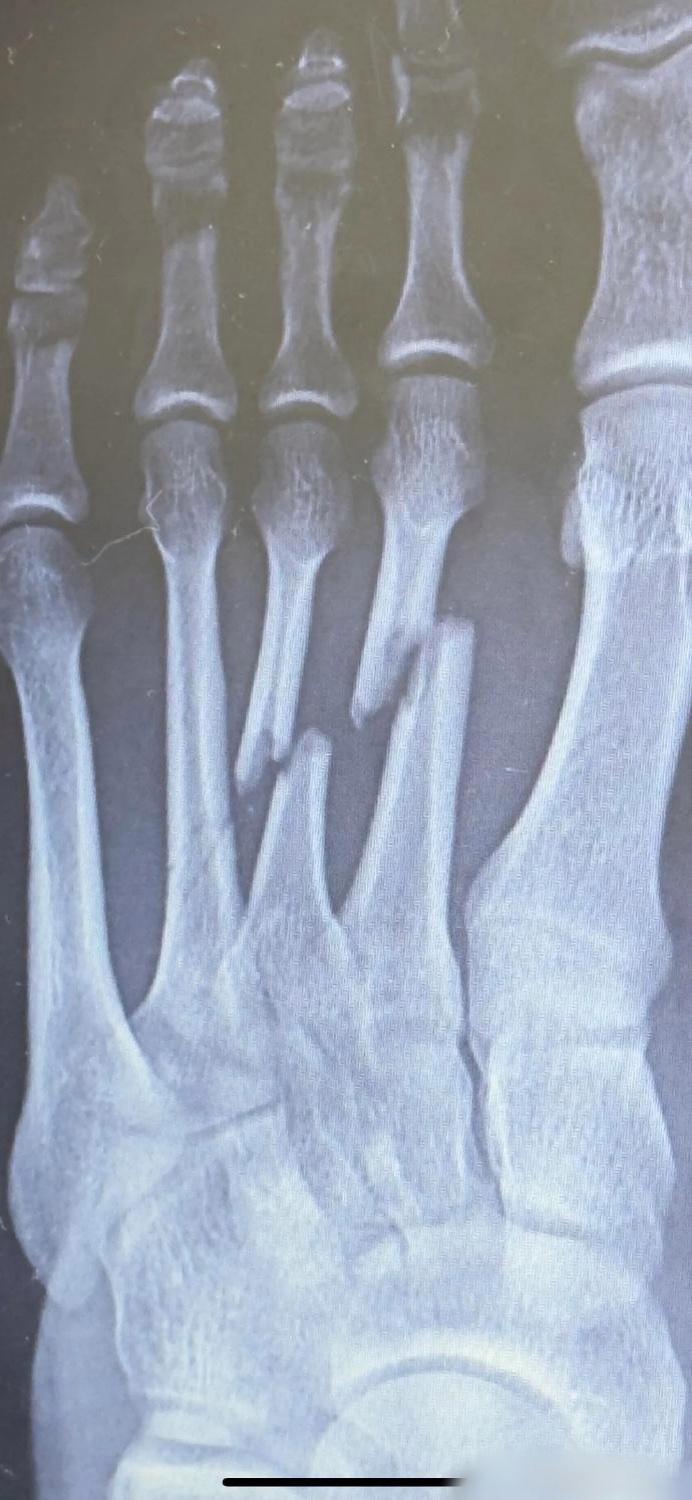

鼻骨![白眼] 这件事,很多人不明白! 生活中,有时候鼻子受伤,鼻梁肿胀,鼻孔出血,去医院拍一张鼻部CT,医生诊断鼻子有骨折,咱老百姓不专业,认为鼻子骨折,就是“鼻骨骨折”,其实这是不对的。 从解剖结构上,鼻子凸出在面部,去除表面的肉,露出下面的骨头,其实它可不是一整块,它由多个骨头构成,如图所示,分别为额骨、鼻骨、上颌骨、鼻中隔,各块骨头均有自己的名称,每个都是一个独立的解剖个体,所以它们骨折,应该分别叫“鼻骨骨折、上颌骨额突骨折、鼻中隔骨折”。 但有一点要注意,几个参与鼻子构成的骨头拼凑在一起,彼此之间就会有边界,就会有缝隙,这些缝隙通过鼻CT可以显示,正因为这些缝隙的存在,有的医生会误诊为骨折,这个情况,在生活中要注意。 白话科普文章,感谢阅读,进入空间,其他文章更精彩![作揖]